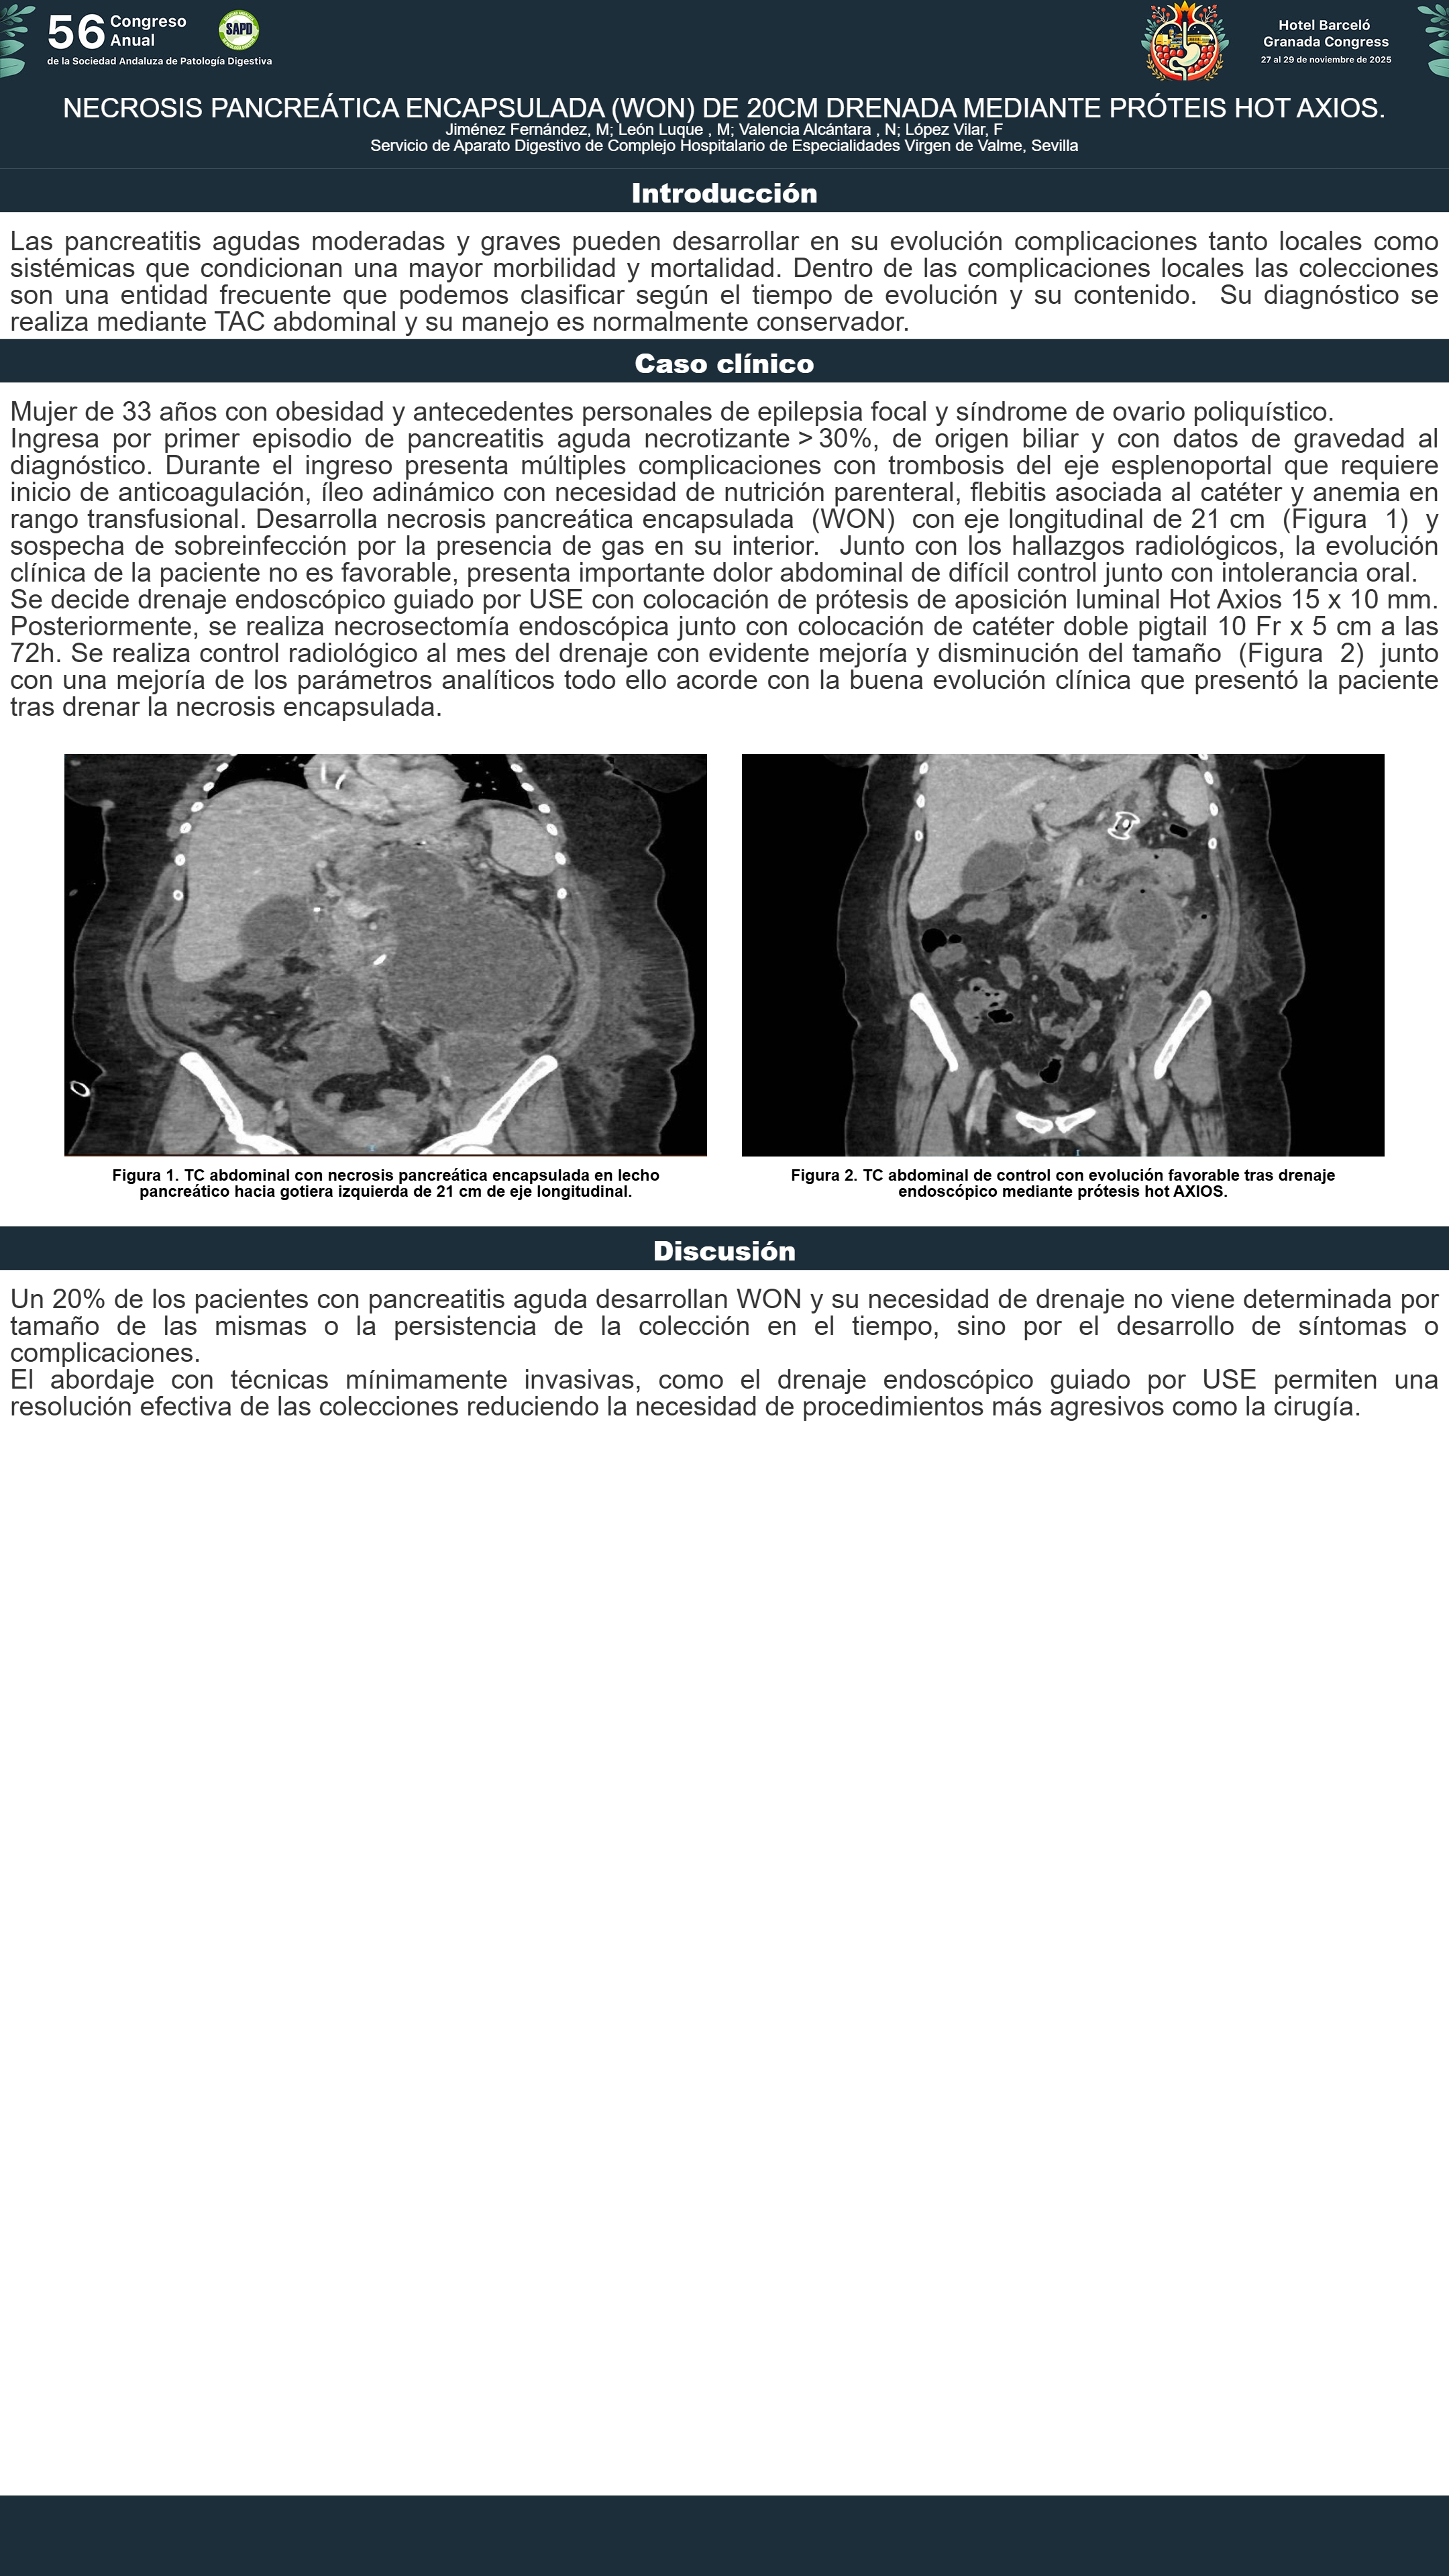

[CP-163] NECROSIS PANCREÁTICA ENCAPSULADA (WON) DE 20CM DRENADA MEDIANTE PRÓTEIS HOT AXIOS.